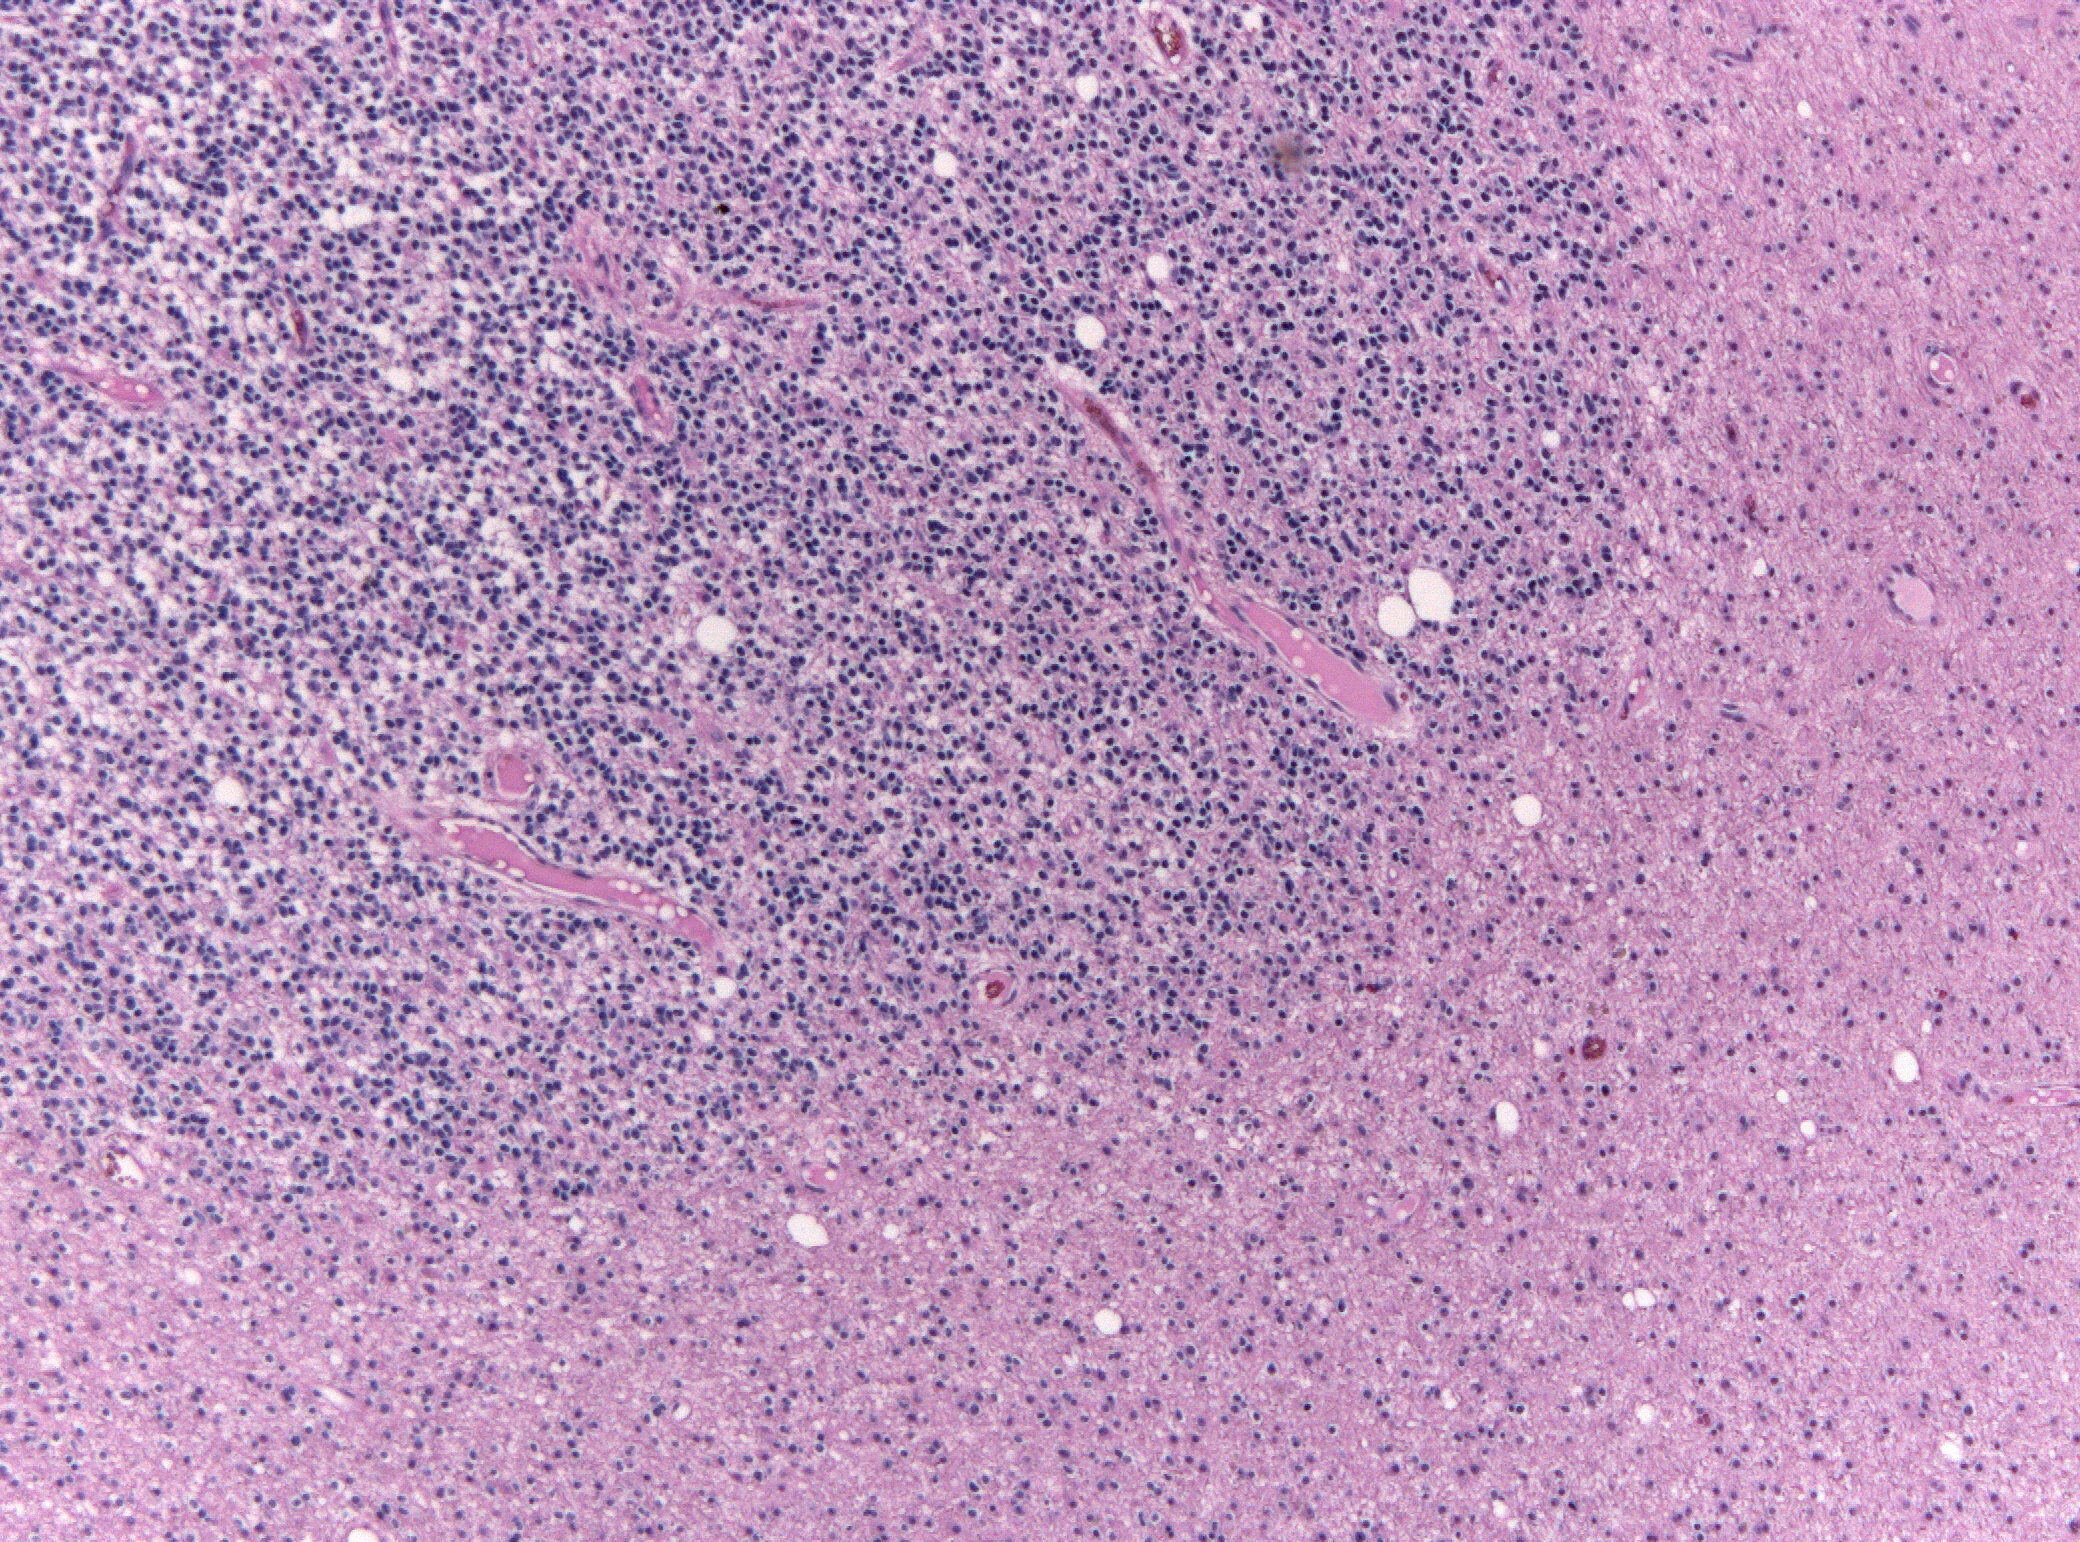

Микрофотографии гистологии глиобластомы головного мозга